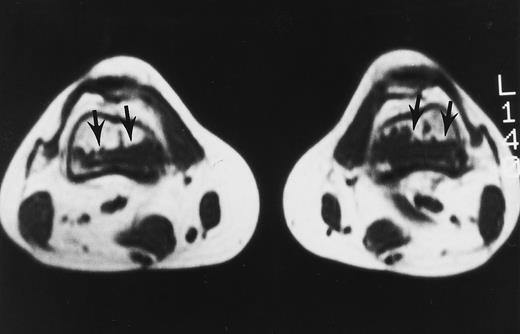

A 32-year-old woman with AML and biopsy-proven fibrosis in the marrow. T1-weighted (500/10, TR/TE) axial MR image of the distal thighs shows foci of fibrosis (arrows) with dark signal. On T2-weighted MR images (not shown), the signal of the lesions did not change.